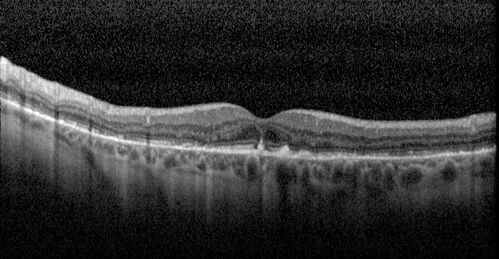

Elmiron (pentasosan polysulfate) Macular Toxicity

77 year old female who had been on Elmiron for 20 years and stopped it 2 years ago